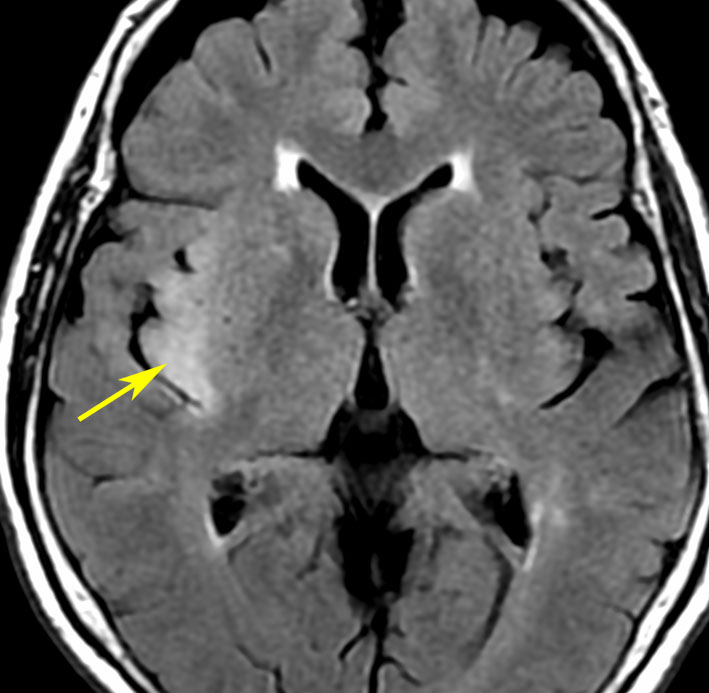

まずMRIで診断です

右側頭葉島の病変です。1年間の経過ではっきり増大したので,無症状でしたが生検術を行いました。病理組織では,異型グリアの増殖はありましたが,核分裂蔵,血管内皮の増生や壊死は明らかではありませんでした。しかし,遺伝子診断ではIDH1/2 野生型,ATRX retained,TERT promotor野生型,1p/19q共欠失なしでした。膠芽腫という確定病理診断です。

標準治療を加えましたが,数ヶ月後に急激な増大を呈しました。グレード4の臨床像です。MRI画像よりも病理組織像よりも,遺伝子診断の方がより性格に予後を示す例です。

診断:MRIでの特徴

• 診断はMRI検査をします,それだけで十分です

• ガドリニウム造影剤で腫瘍の周辺が白く造影されます

• いびつな形になるのが特徴です

• しかし,ほんとうの腫瘍の広がりは,T2強調あるいはFLAIR(フレア)という画像で,白く滲むように写る部分すべてです

• 手術でガドリニウム増強される部分が全部取れると,お医者さんは全摘出できたといいますが,それは間違いです

• FLAIR画像で白く見える部分が全て取れてはじめて,画像上での全摘出と言えます

• それでもなお,隠れた腫瘍細胞は周囲に滲み込んで残っています

典型的な膠芽腫のガドリニウム増強画像です。右の側頭葉から発生したために目立った症状が無く,この大きさで発症しました。何となくボッとしていると言うのが訴えでした。腫瘍の周囲がガドリニウムで白く増強されて,内部は壊死で低信号(黒っぽい)になっています。

左がガドリニウム増強像で,手術ではこの部分が取れれば全摘出といわれるのですが,実際は右側のフレア画像で白っぽく見える所には腫瘍が滲み込んでいます。この部分を全て摘出してはじめて,画像上の全摘出といいます。全摘出は無理でしょう